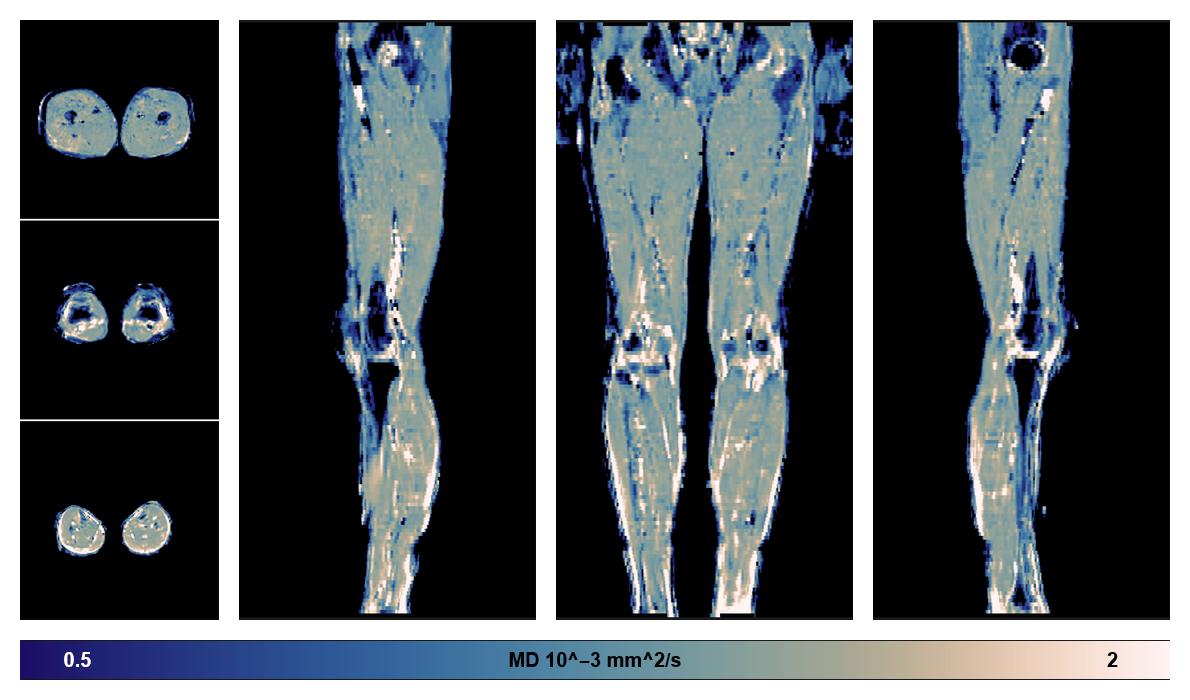

Diffusion tensor imaging

Diffusion weighted imaging with IVIM and DTI fitting to obtain muscle microstructure and muscle architecture, for information look here».

• Mean diffusivity

IVIM corrected whole leg muscle mean diffusivity obtained from diffusion tensor imaging.